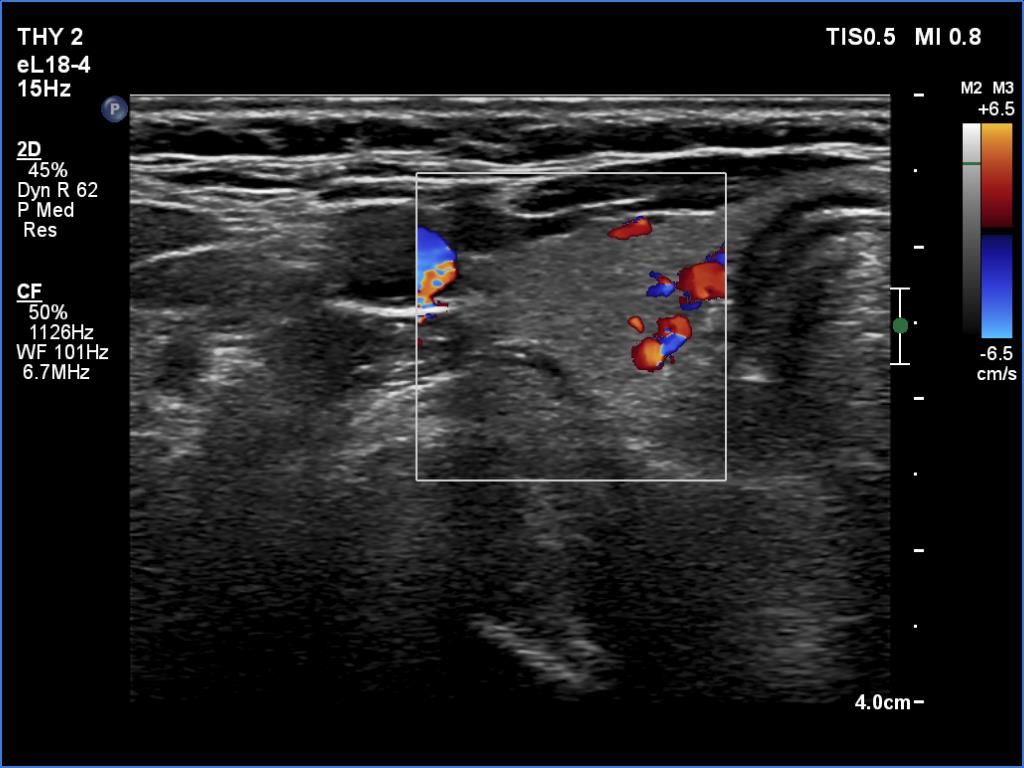

Second examination 6 month later (2nd row of images)

Clinical presentation. The patient was referred for evaluation of hyperparathyroidism. Elevated calcium and parathyroid hormone levels were found during the first evaluation. (These findings were not yet available when I first examined the patient.) Further evaluation disclosed a hyperfunctioning right lower parathyroid. The patient was operated on but no parathyroid tissue was found on histopathology. (A more experienced parathyroid surgeon was quarantined at the scheduled time of the operation, so a less experienced colleague performed the surgery.) Both hypercalcemia and hyperparathyroidism have persisted.

Ultrasonography revealed a hypoechoic mass corresponding to the right lower parathyroid.